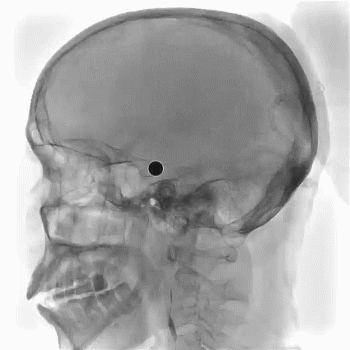

在泥鳅导丝导引下,用4F多功能管携8F导引导管直接进入左颈内动脉C1近段,血管迂曲8F导引导管无法进入左侧颈内动脉C1远端,遂取6F多功能管Navien,置于颈内动脉岩骨段,取微导丝在微导管辅助下小心通过血栓闭塞段到大脑中动脉M1,微导管在微导丝辅助下送大脑中动脉M1段,退出微导丝,将NeuroHawk®6030取栓支架在透视下放入左侧颈内动脉末段闭塞段并释放支架取栓,支架打开欠满意,闭塞段可见一重度狭窄,考虑血管慢性狭窄闭塞,予替罗非班0.625mg静脉推注后,持续静脉内0.4mg/h泵入,约8分钟后予撤出支架及微导管,此过程中用50ml注射器保持负压抽吸血液,取栓次数1次,取出一0.2cm×0.5cm血栓。

术中正侧位

复查造影提示左侧颈内动脉C7段重度狭窄,远端血流速度可,未见乏血管区,TICI分级3级(穿刺至再通1.28h),行DynaCT未见明显高密度影;观察10分钟、30分钟分别行脑血管造影提示左侧颈内动脉狭窄无明显回缩,远端血流可,继续替罗非班0.4mg/h持续泵入,从穿刺到结束手术1小时59分。术后患者苏醒满意,双侧瞳孔等大,疼痛刺激右侧肢体可见少许活动。

术后正侧位